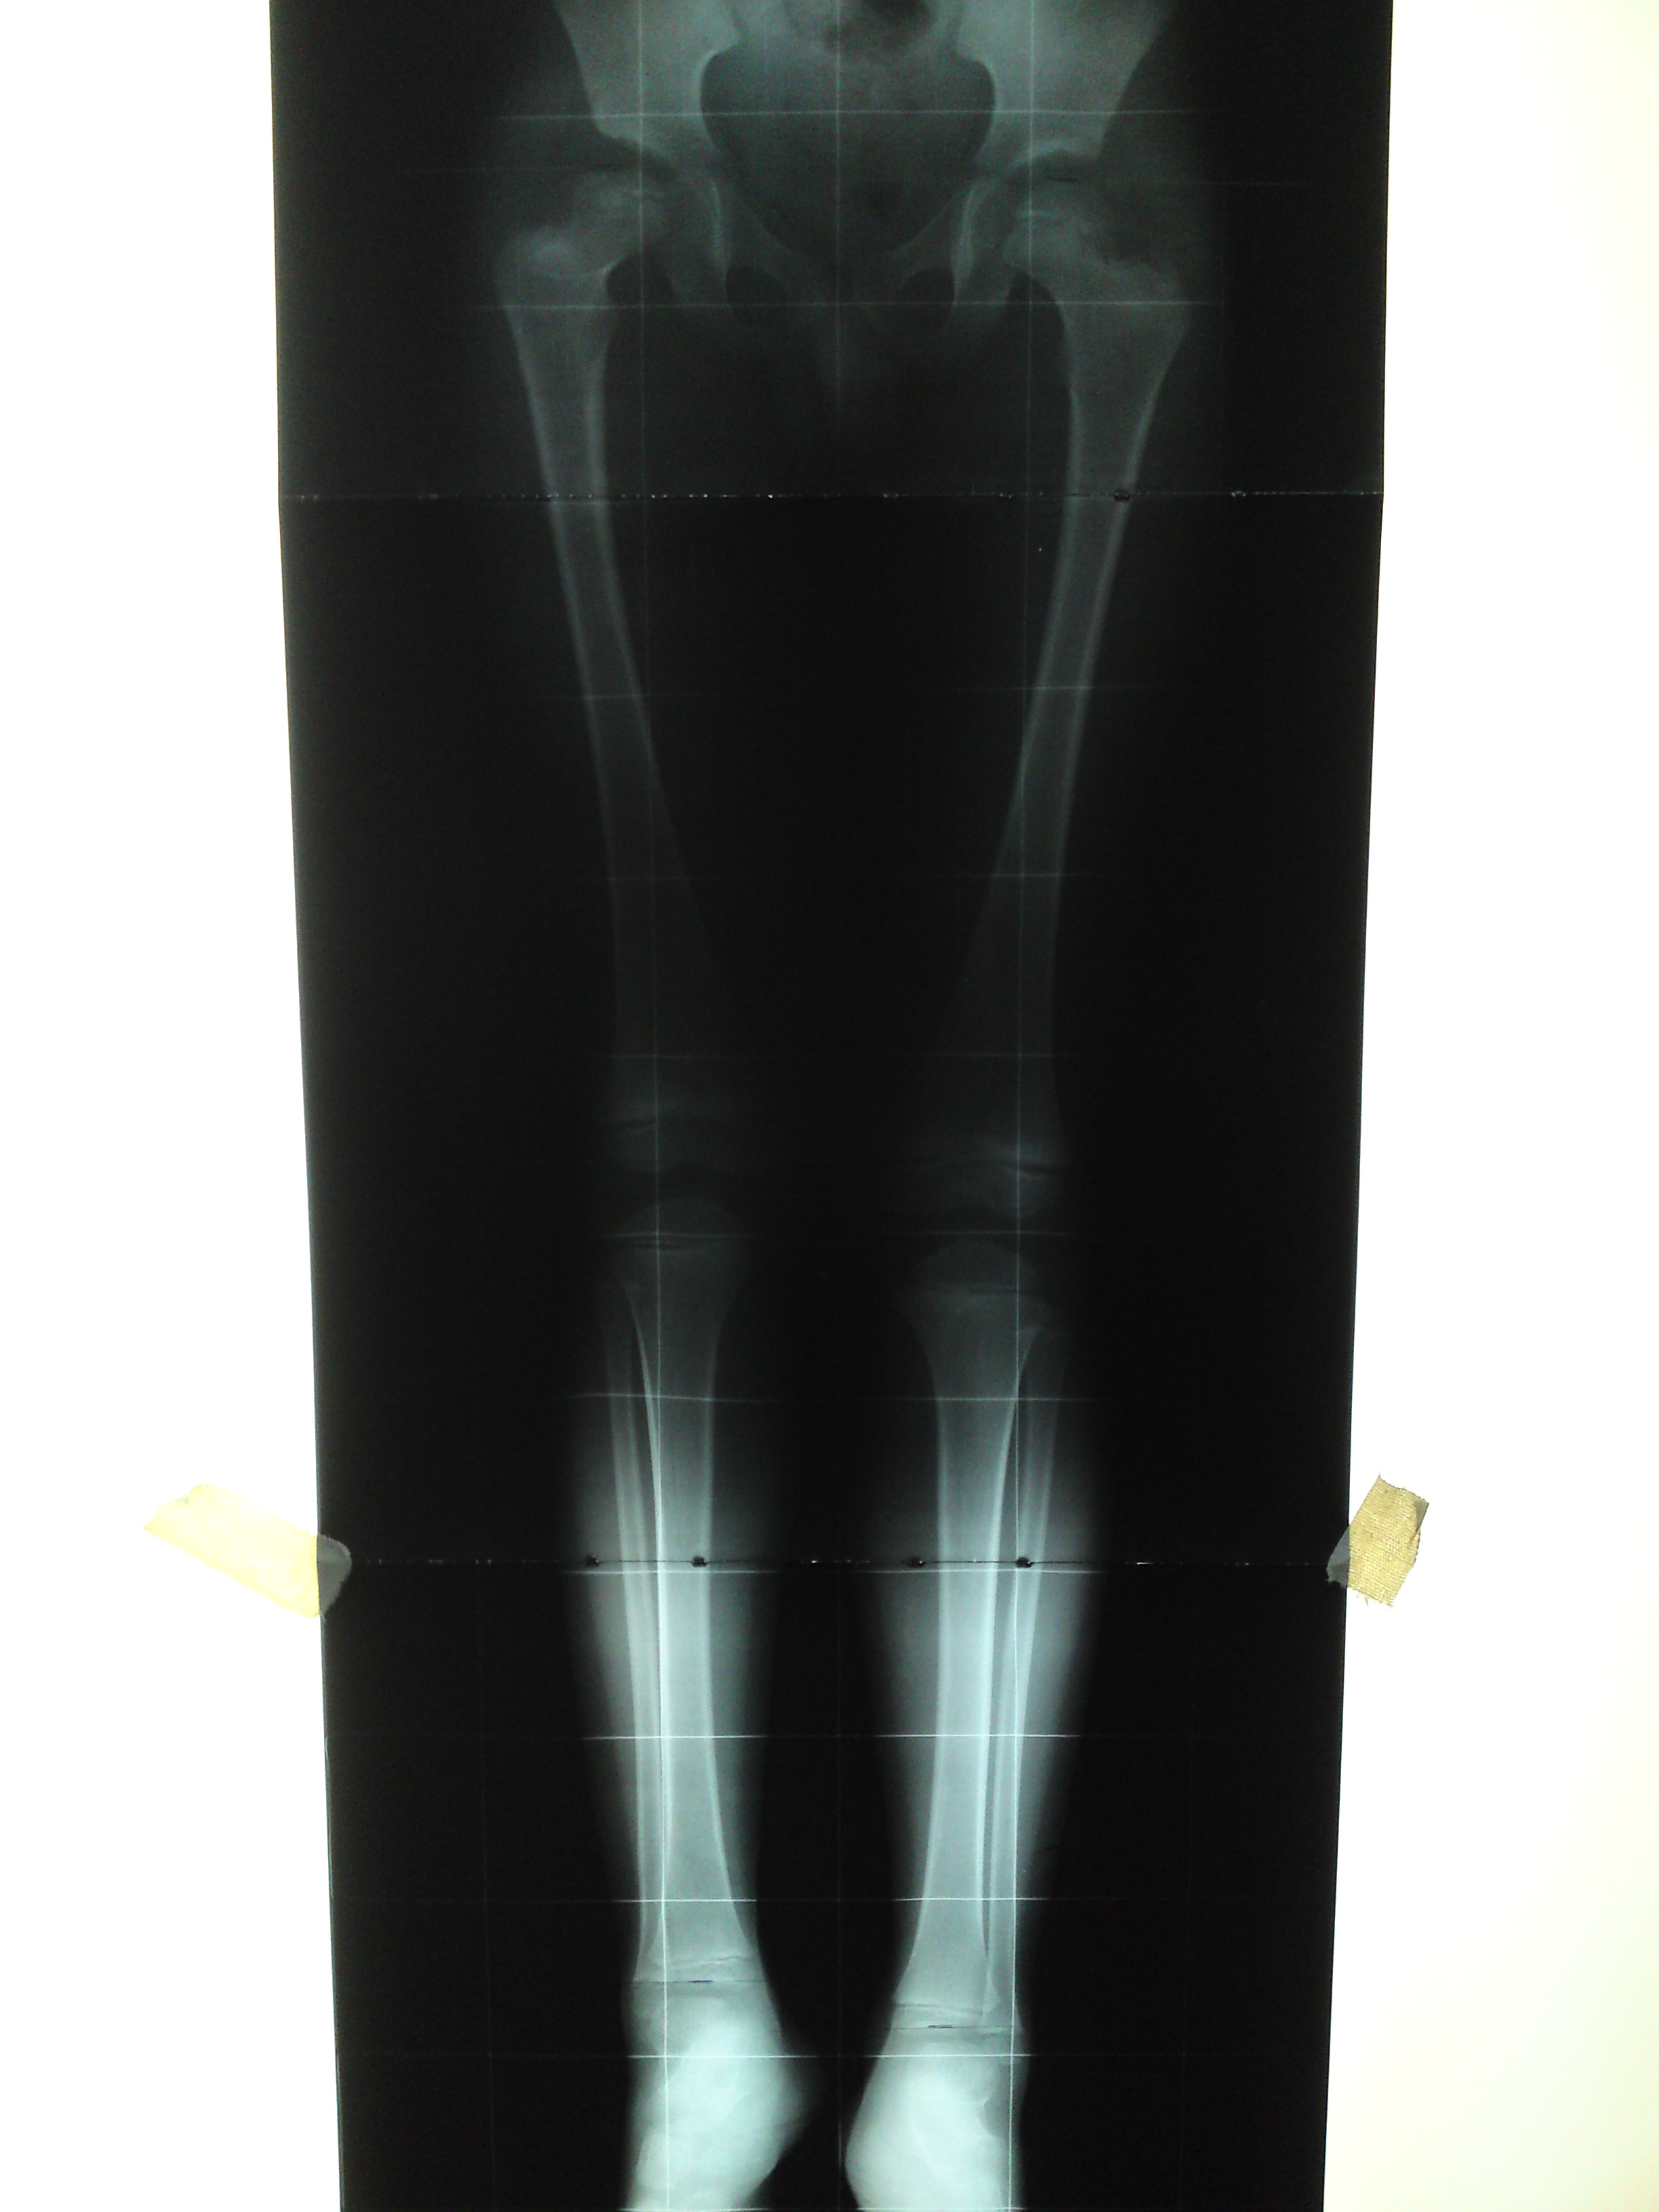

Growth Modulation in Renal Osteodystrophy